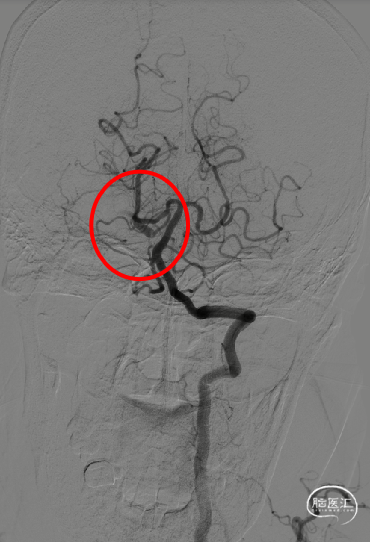

8F导引导管在多功能管及泥鳅导丝导引下直接进入右侧颈总动脉,此时Skathi远端通路导管尾端连接自制50ml负压注射器一路裸奔抽吸至C5段,反复抽吸3次,抽出大量血栓,回血通畅后,轻轻冒烟提示颈内动脉通畅,大脑中动脉M1远端闭塞,与取栓前后循环造影显示情况一致。

大脑中动脉M1段血栓采用SWIM技术-抽拉结合,避免血栓逃逸。

一次SWIM取栓,成功血管再通,达到mTICI分级:3级。

对于血栓负荷量大的前循环卒中患者,需要考虑更短的手术操作时间、保护血栓的完整性,尽量避免造成远端二次栓塞。远端二次栓塞再次补救不仅会增加患者的经济负担,而且也增加了术后并发症发生的风险,ADAPT技术应该是首选方式。

Skathi远端通路导管通过性较好,可以上到较高节段直接接触血栓进行抽吸,此外,其大口径的特点能增加其与血栓的接触面积,增加取栓成功率,减少血栓逃逸。而且管腔的抗疲劳性也较好,能够耐受多次抽吸管腔不变形。